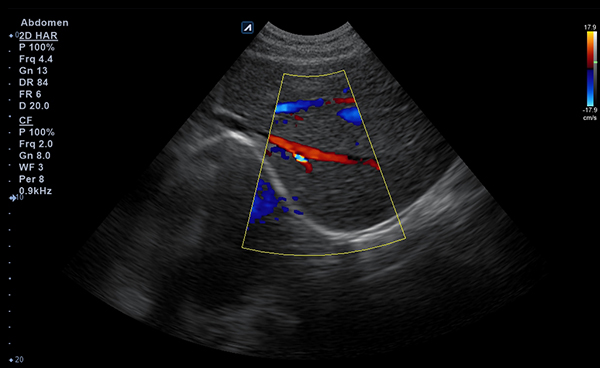

Alpinion Medical Systems, la empresa de sistemas de ultrasonido, ha combinado tecnologías

de procesamiento de imágenes y transductores para garantizar que minisono proporcione

imágenes 2D de alta definición e información de Doppler más claras y nítidas.

- Imaging modesB-mode, CF, M, PW, PD